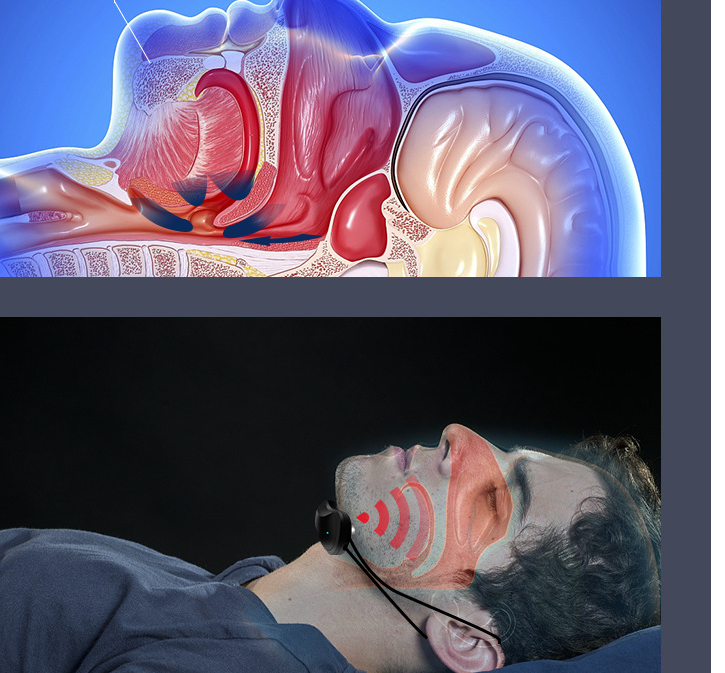

Intelligent Anti-snoring Device

Intelligent Anti-snoring Device

Pulse frequency: 10HZ-1500Hz